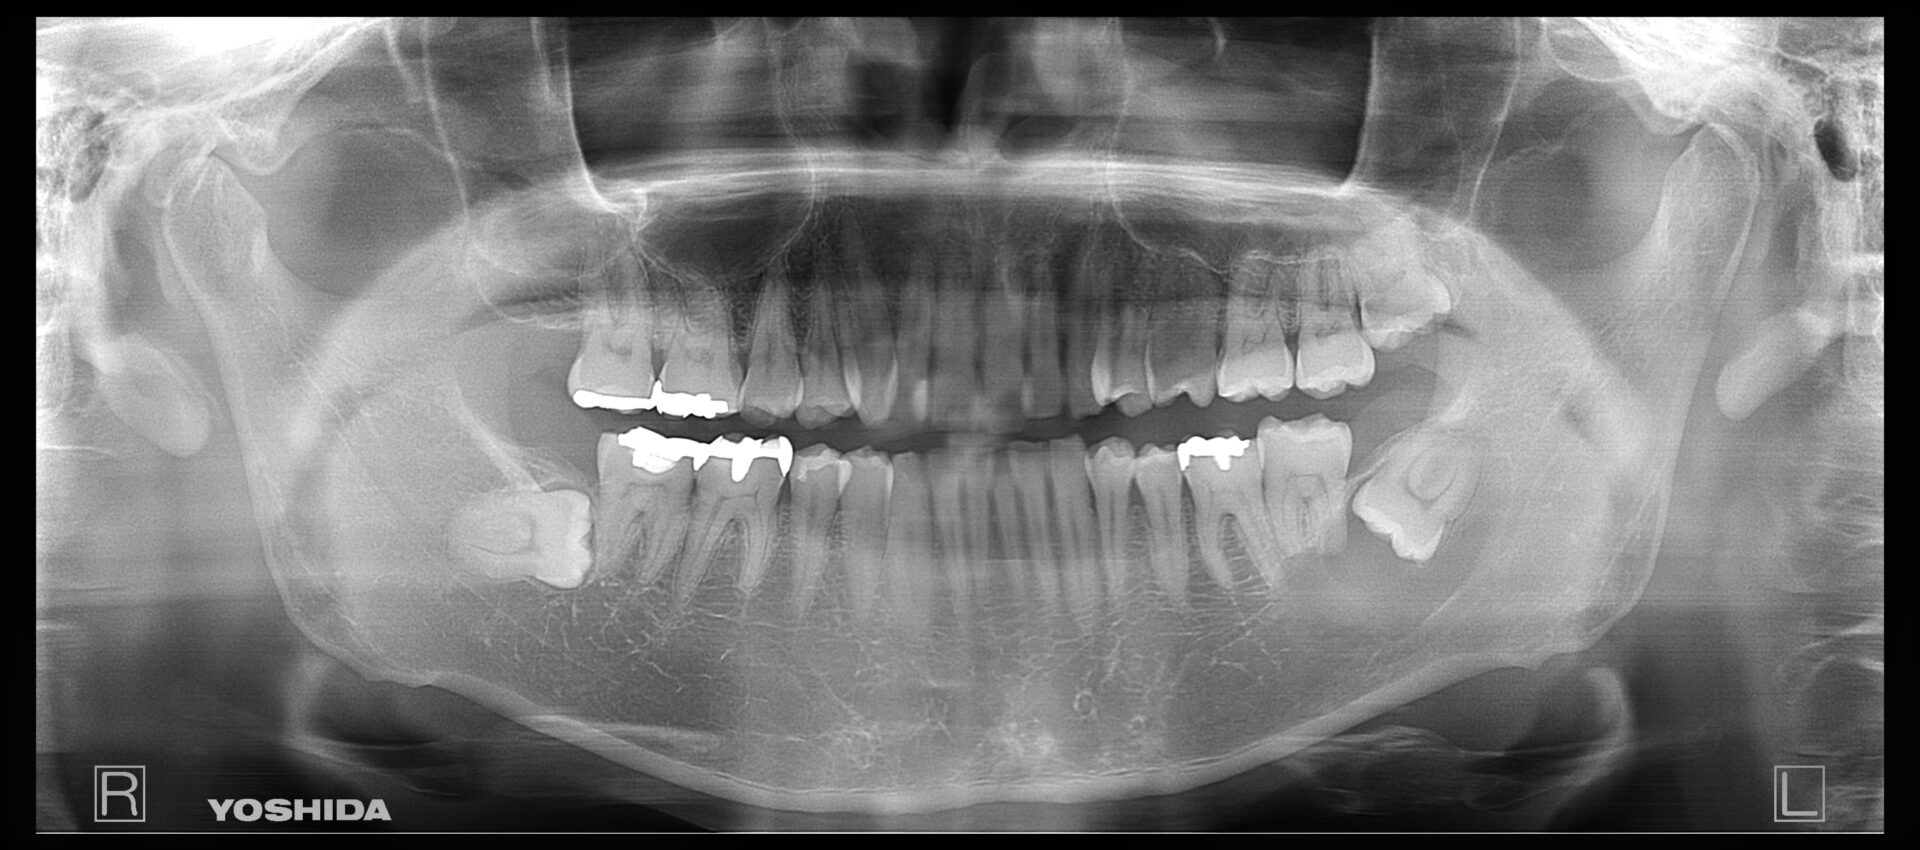

30代女性

2021/12

2025/8 右上6番にインプラントを埋入

2022/1

2025/8 右上6番はインプラント上部でフルジルコニアを、右上7番もフルジルコニアを使用しています。

治療部位 | 右上6、7番 |

費用 | 約55万円円 |

治療期間 | 10ヶ月 |